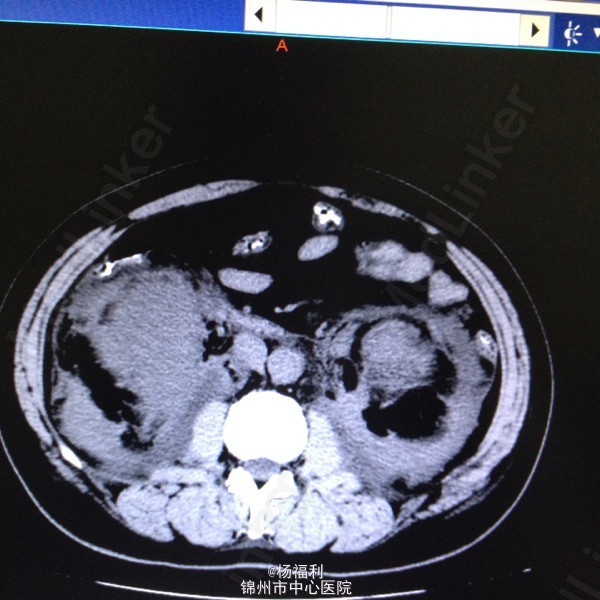

44岁女患。为消化科我会诊患者。 现病史:以上腹痛9小时为主诉入院。无发热及寒战、噁心未呕吐,无腹泻及黑便。 既往史:双眶炎性假瘤2年,口服激素治疗,并补钾。

查体:上腹部压痛,无反跳痛、右侧压痛明显,右肾区叩击痛,左肾区轻叩击痛,双输尿管走形区无压痛。 辅助检查;泌尿系彩超:双肾积水。 血白细胞:9.99*10^9。 肾功能正常。 全腹部ct及MRU检查:见图片。

诊断;真的不知道是啥病。 处理:暂时止痛处理。双肾病变。不知从哪里下手。